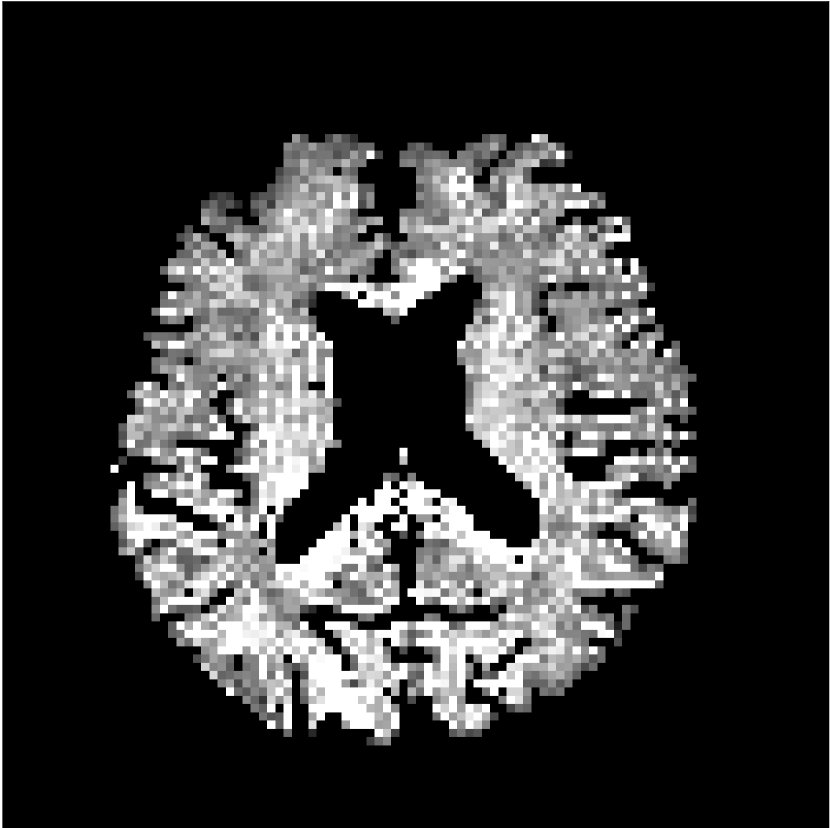

Figure 8 shows examples of non-diffusion-weighted images before and after processing. The raw images (Raw) served as the input for the magnitude deep learning (MCNN) and complex deep learning (CCNN) methods.

Raw

MCNN,

MCNN Resid.,

CCNN,

CCNN Resid.,

No PF

5/8 PF

Both methods remove artifacts, but the MCNN method allows residual rippling artifacts to pass through in the presence of partial Fourier. These rippling artifacts are not present in the CCNN method.